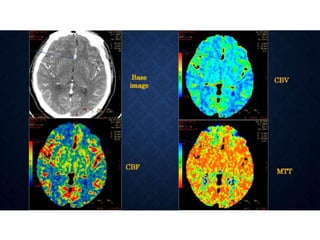

NORMAL PERFUSION

• Blood Flow or Perfusion

• • Flow rate through vasculature in tissue region (mL per 100 g/min)

• BV or Blood volume

• • Volume of flowing blood within a vasculature in tissue region (mL per 100 g)

• MTT or Mean transit time

• • Average time taken to travel from artery to vein (Seconds)

• MTT can be approximated according to the

central volume principle: MTT = CBV / CBF.

 Color-coded perfusion maps of cerebral blood volume,

cerebral blood flow, and mean transit time are then generated

at the workstation